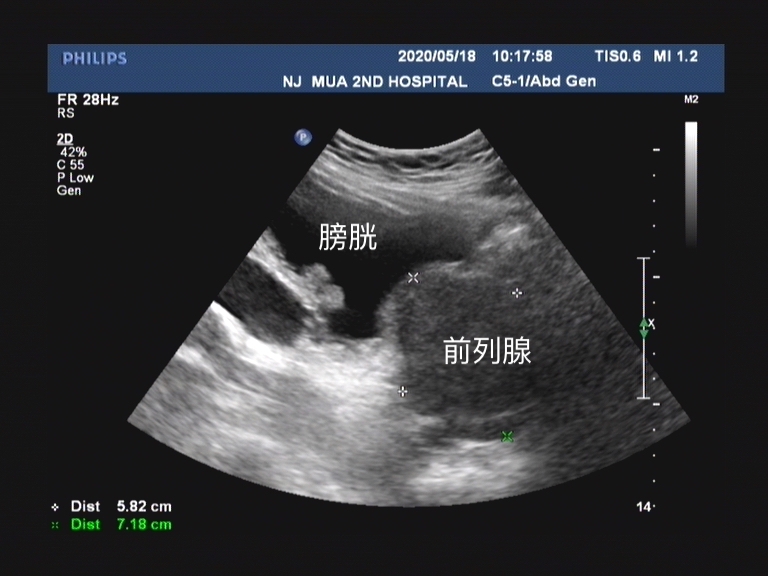

彩超下的前列腺增生表现,体积增大,向膀胱内凸出